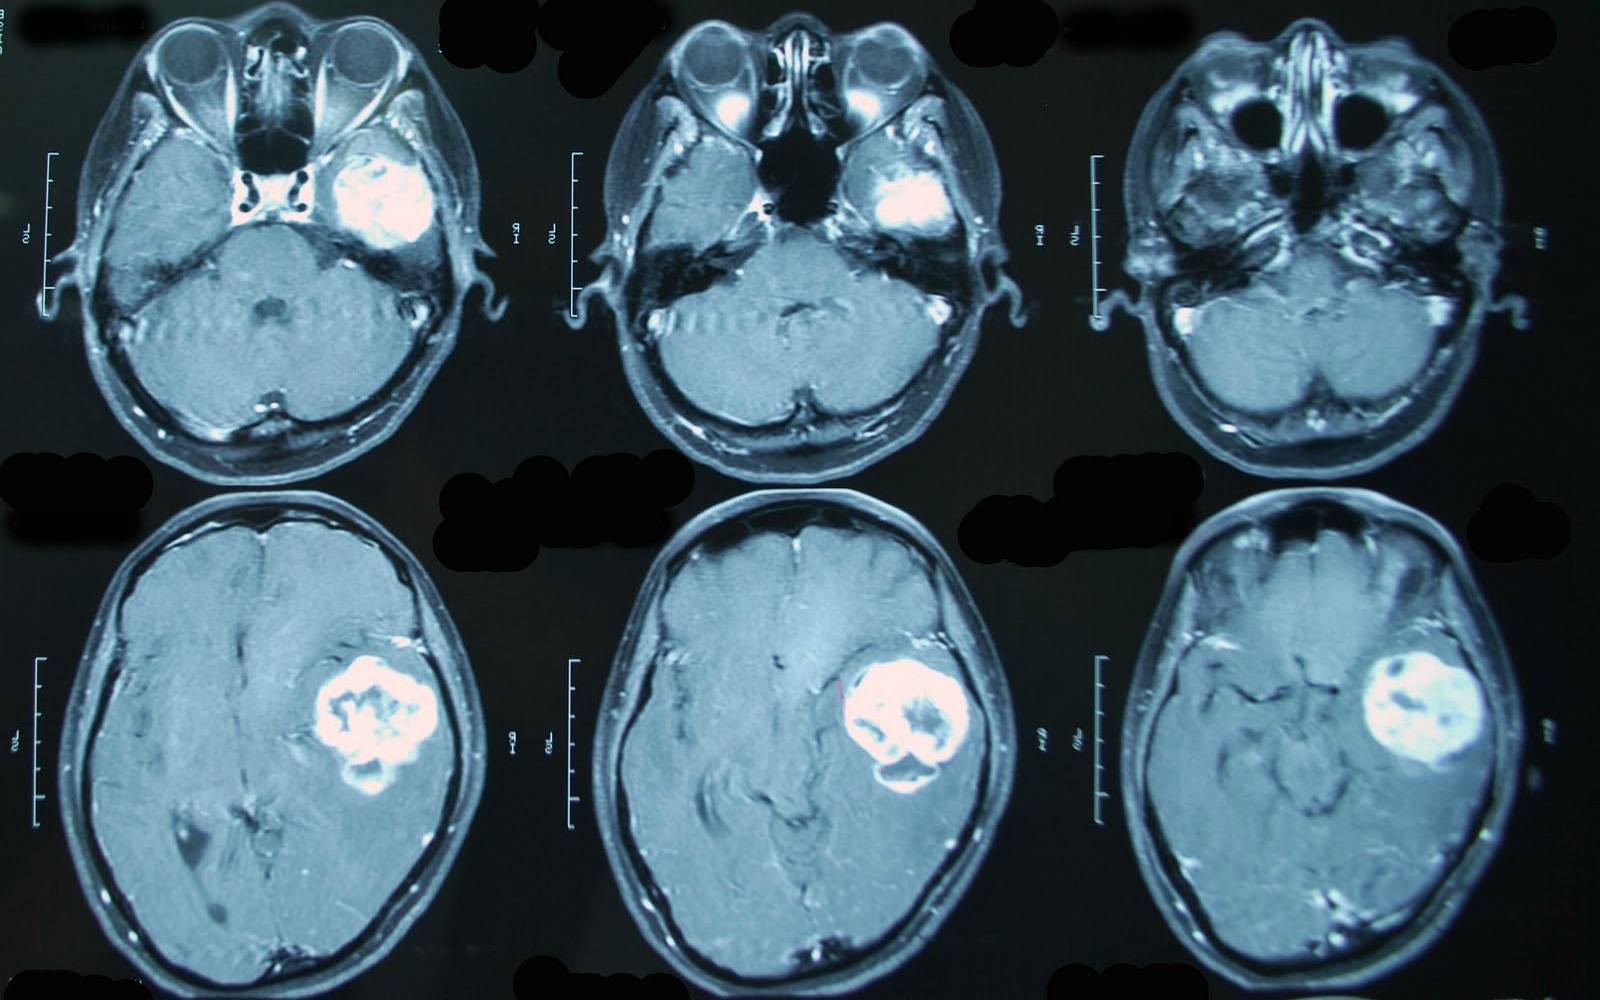

МРТ головного мозга с контрастом обязательно при диагностике онкологических процессов.

На основании этих проекций формируется представление о реальных физических размерах, взаимном месторасположении, структуре и состоянии любого внутреннего органа. По МРТ-снимку можно локализировать опухоль с диаметром от 1 миллиметра, найти внутреннее кровотечение, травматическое изменение в тканях или патологию их развития, очаг воспаления и зону инфекционного поражения. Если во время сканирования в кровь пациента ввести контрастное вещество, проекция виртуального среза станет более отчетливой — диагност наведет «резкость» на снимке, повышая точность прогнозов.

Процесс проведения МРТ с контрастом

Пигментное вещество, вводимое в кровь пациента, заставляет ткани новообразований изменить цвет на мониторе томографа, проявляя себя даже при незначительном размере опухоли. Контраст подсвечивает метастазы, вскрывает проблемы послеоперационного периода, фиксирует кровотечения и аномальные скопления жидкости в тканях, окружающих внутренний орган.

Несмотря на то, что этот неинвазивный и высокоэффективный способ диагностики можно использовать в любой отрасли медицины, преимущественно контрастную магнитно-резонансную томографию назначают для выявления опухолей.